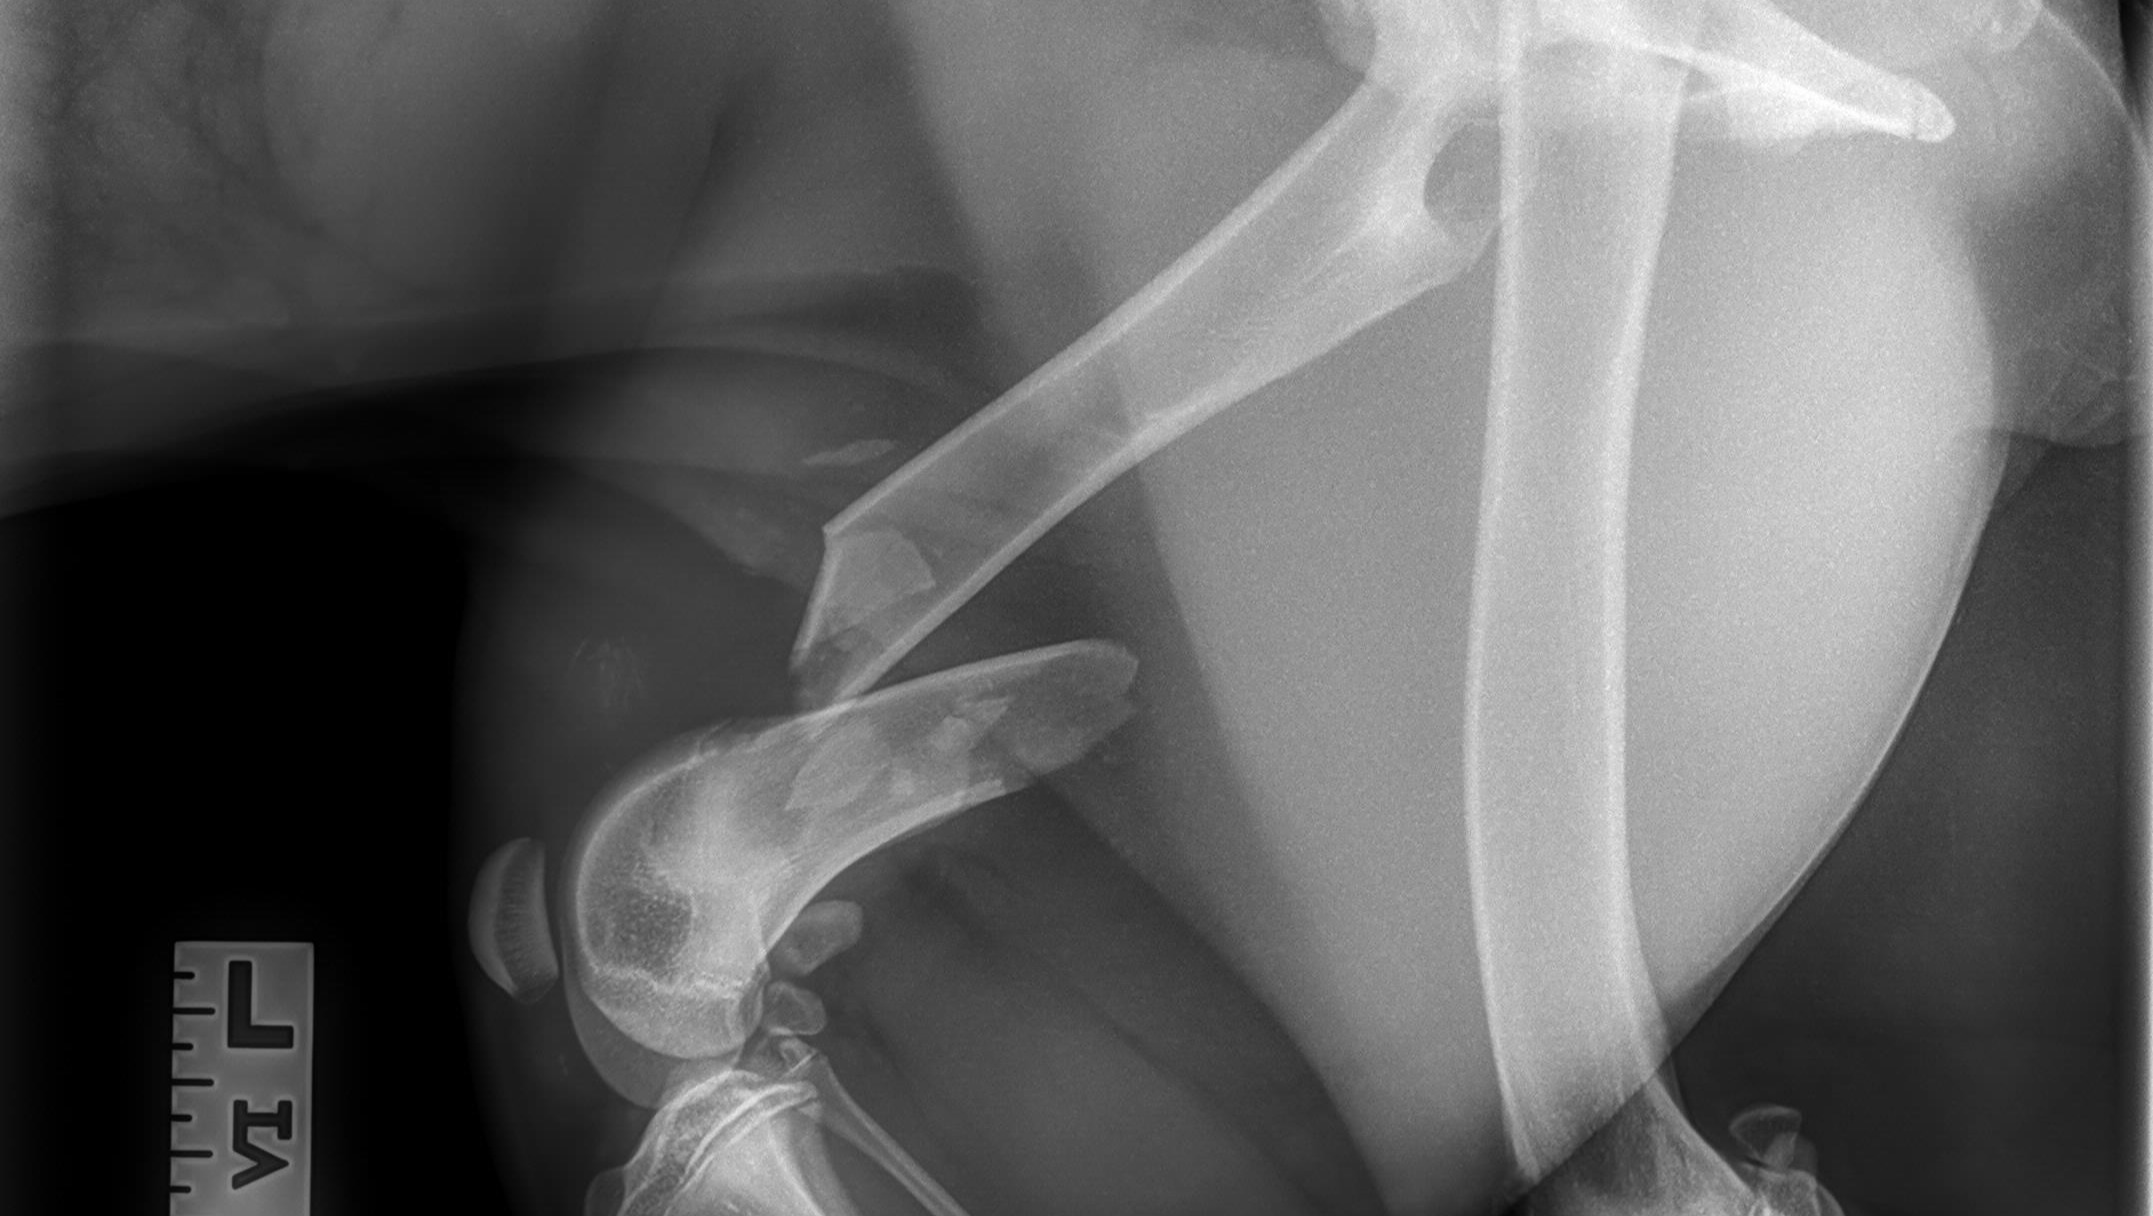

A few days ago, I found Honey on the side of the freeway after being hit by a car. She was beyond sweet and despite the pain, got up to greet me and snuggled between my legs. I immediately took her to the vet where they performed X-rays and determined she has a broken femur, a deep lesion on her tarsus, a dislocated tail, and paralysis of her hind end. This is all in addition to the malnutrition and dehydration she was suffering from due to being a stray for some time. She needs urgent orthopedic surgery to fix her femur, antibiotics for the lesion, and probable amputation of her tail. We've been reaching out to rescues to help, but she will likely be incontinent for the rest of her life so they're hesitant to help. She will need extensive care for the remainder of her life which we are more than happy to provide. She's already a member of the family. We really want to keep her, but she desperately needs these surgeries that we simply cannot afford right now! We're also worried that if we take her to a shelter they will put her down rather than fund these pricey surgeries. We've set a pretty high goal because the surgery is going to be expensive and she's going to require a lot of aftercare including a spay, licensing fees, medication, and measures for her incontinence.